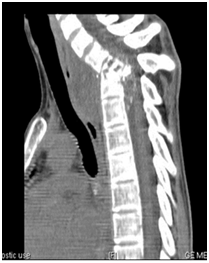

Biology showed a marked inflammatory biological syndrome: erythrocyte sedimentation rate at 130mm/H1, a C-reactive protein at 38mg/l, and a normochromic normocytic anemia at 10 g/dl of hemoglobin. Leukocytes, platelets, blood glucose, serum calcium, creatinine, ionogram, transaminases, muscle enzymes, and lipid parameters were within normal limits. X-rays of the cervical spine showed significant damage of the fifth and sixth cervical vertebrae (C5 and C6) with destruction of the vertebral bodies, narrowing of the joint space and marked thickening of the retropharyngeal space. Cervical computed tomography (CT) confirmed the diagnosis of advanced C5-C6 spondylodiscitis (Figures 1 & 2) and demonstrated a large retropharyngeal abscess exerting a mass effect on aerodigestive structures (Figure 3).

Figure 1 Sagittal cervical CT/bone window: C5-C6 spondylodiscitis with retropharyngeal abscess.